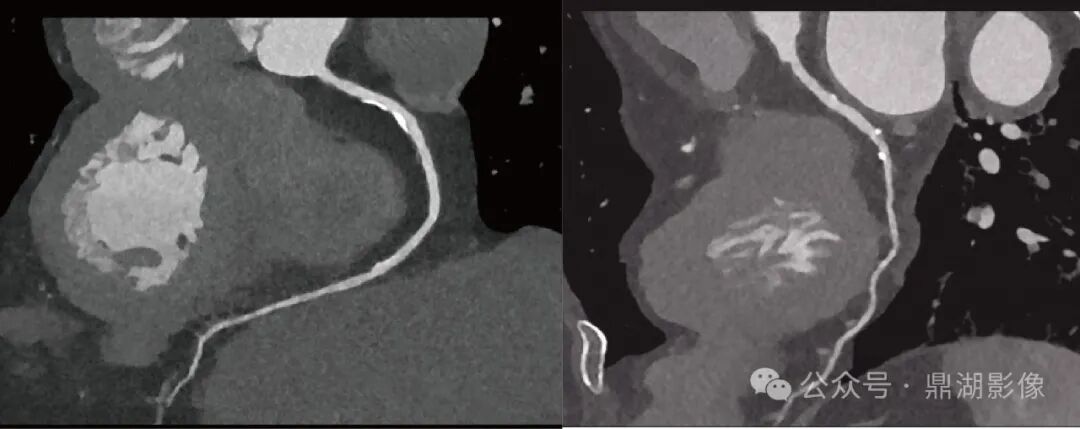

图 冠脉CTA扫描曲面重建(CPR)显示:前降支及左回旋支血管壁多发钙化斑块

冠脉CTA在检测冠脉钙化斑块方面具有极高的敏感性,能够为冠心病的诊断和治疗提供重要信息,图像可见左前降支近段血管壁钙化斑块,NeuViz Epoch Elite超高清扫描可更精细的显示斑块的形态、密度、分布,为动脉粥样硬化进展监测和血运重建策略提供关键依据。

图 头颈CTA扫描曲面重建(CPR)显示:右侧颈内动脉虹吸段血管壁钙化斑块

CT高清扫描在头颈部血管疾病中兼具解剖与功能评估优势,是脑血管病筛查、诊断及治疗规划的核心工具,NeuViz Epoch Elite超高清模式可更精细的显示头颈部血管的解剖结构复杂,包括颈动脉、椎动脉、Willis环等结构。